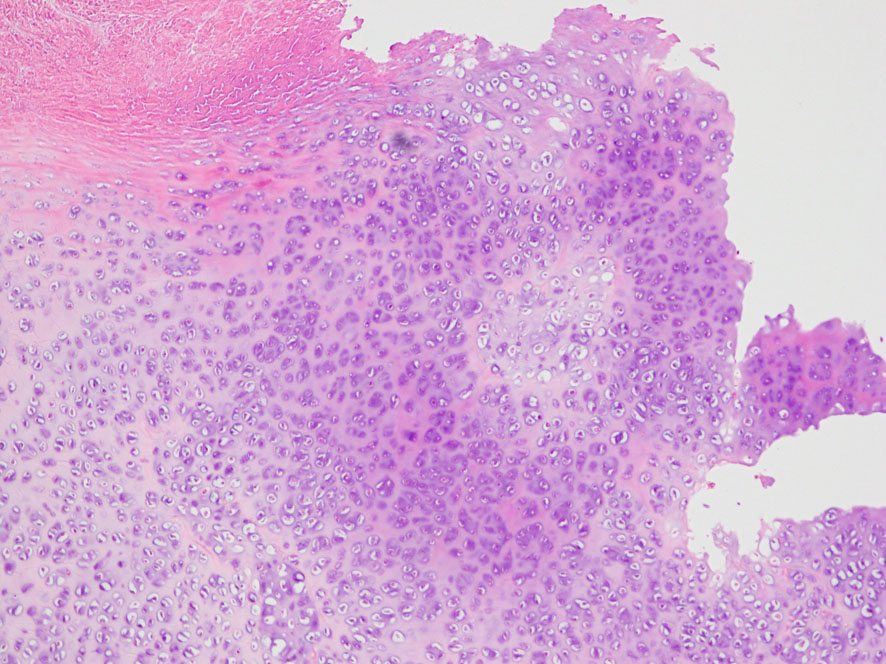

照射後の奇形腫の病理像

左上にはcartilage,右上にはkeratin squamous tissueがみられます。左下は繊維生組織のみdense collagenous tissueです。

生検術で胎児性癌と未熟奇形腫の混合型と診断されたために,化学療法と61.1グレイの放射線治療がなされていました。しかし,大きな松果体腫瘍が残り全摘出したものです。この子の腫瘍は治っていて元気に暮らせています。

奇形腫の照射後はいつもそうなのですが,dense collagenous tissueとfibroblastic spindle cellが組織の主体となっています。要するに肉芽腫のようなものです,ですから,手術摘出ではものすごく硬い線維性の腫瘍となっていてハサミでも切れずに難渋します。出血もしないし脳とは剥離できるのできます。放射線化学療法前の生検による組織像(悪性要素)は消失して単なる成熟奇形腫との病理診断となってしまいます。しかし,この組織のどこかに悪性度の高い細胞が潜んでいて,播種再発するなどということも経験しました。放射線治療後の病理組織診断はその後の予後の予想のためには役に立ちません。